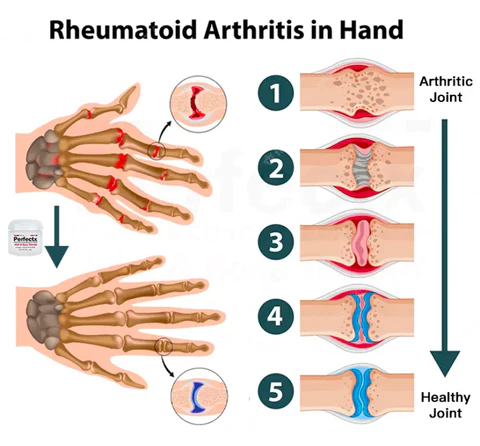

Jennifer Betz: “After years of suffering from rheumatoid arthritis in my hands, I am overjoyed to find that treating it is so simple and straightforward. It has been such a relief to be able to find an effective way of managing my condition and it has given me a newfound sense of hope and freedom.”